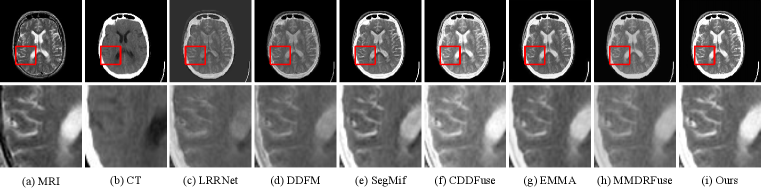

For MIF, we show the qualitative comparison in Fig. 10, 11 and 12. Our method fully integrates the detailed information of MRI images and the functional information of the other images. As shown in Fig. 10, our method clearly demonstrates the detailed information of the MRI images. As shown in Fig. 11 and 12, our method not only preserves the color information but also achieves higher contrast. This makes it much easier to observe the images for better medical diagnosis.

Refer to caption

Figure 7: Comparison of fusion results on the MSRS dataset. The second row shows the enlarged regions in the first row.

Figure 8: Comparison of fusion results on the M3FD dataset. The second row shows the enlarged regions in the first row.

Figure 9: Comparison of fusion results on the FMB dataset. The second row shows the enlarged regions in the first row.

Figure 10: Comparison of fusion results on the MRI-CT Harvard Medical dataset. The second row shows the enlarged regions in the first row.